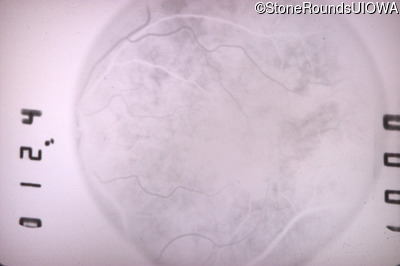

Fluorescein Angiography - Right - 20/25 +2 sc

Exemplar